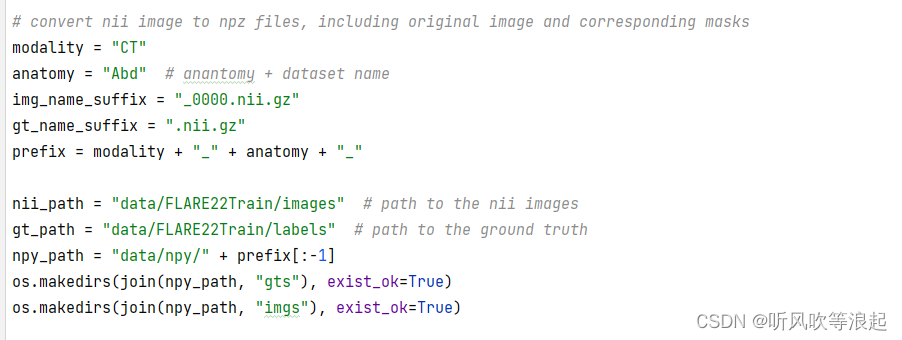

5.3 数据预处理

预处理代码是 pre_CT_MR.py,需要先下载库文件

pip install connected-components-3d主要完成下面几个作用,划分数据集、进行窗口w和窗口h的灰度增强、归一化、resize以及保存到npy的2d格式

这里的预处理脚本完全根据MICCAI FLARE22 挑战数据集数据集格式编写的,如果换成自己数据集的话,需要更改。其实就是目录啊、文件名之类的参数